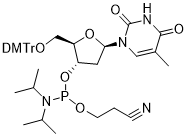

馬鞍山致研生物醫(yī)藥科技有限公司成立于馬鞍山市鄭浦港新區(qū)現(xiàn)代產(chǎn)業(yè)園。公司專(zhuān)注于生物小分子、醫(yī)藥中間體相關(guān)產(chǎn)品的研發(fā)和生產(chǎn),產(chǎn)品主要包括DNA亞磷酰胺單體、RNA亞磷酰胺單體、特殊單體以及按照客戶(hù)要求定制的RNA和DNA,并且公司提供定制合成等方面的研究服...

馬鞍山致研生物醫(yī)藥科技有限公司成立于馬鞍山市鄭浦港新區(qū)現(xiàn)代產(chǎn)業(yè)園。公司專(zhuān)注于生物小分子、醫(yī)藥中間體相關(guān)產(chǎn)品的研發(fā)和生產(chǎn),產(chǎn)品主要包括DNA亞磷酰胺單體、RNA亞磷酰胺單體、特殊單體以及按照客戶(hù)要求定制的RNA和DNA,并且公司提供定制合成等方面的研究服...